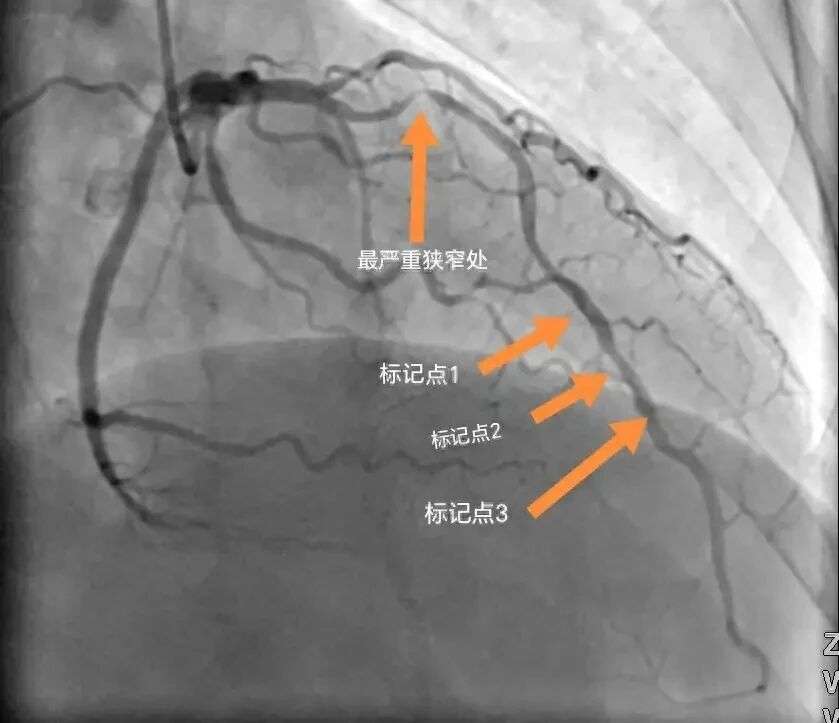

27岁程序员连续熬夜后突发心梗

抢救时发现血管已经堵了80%